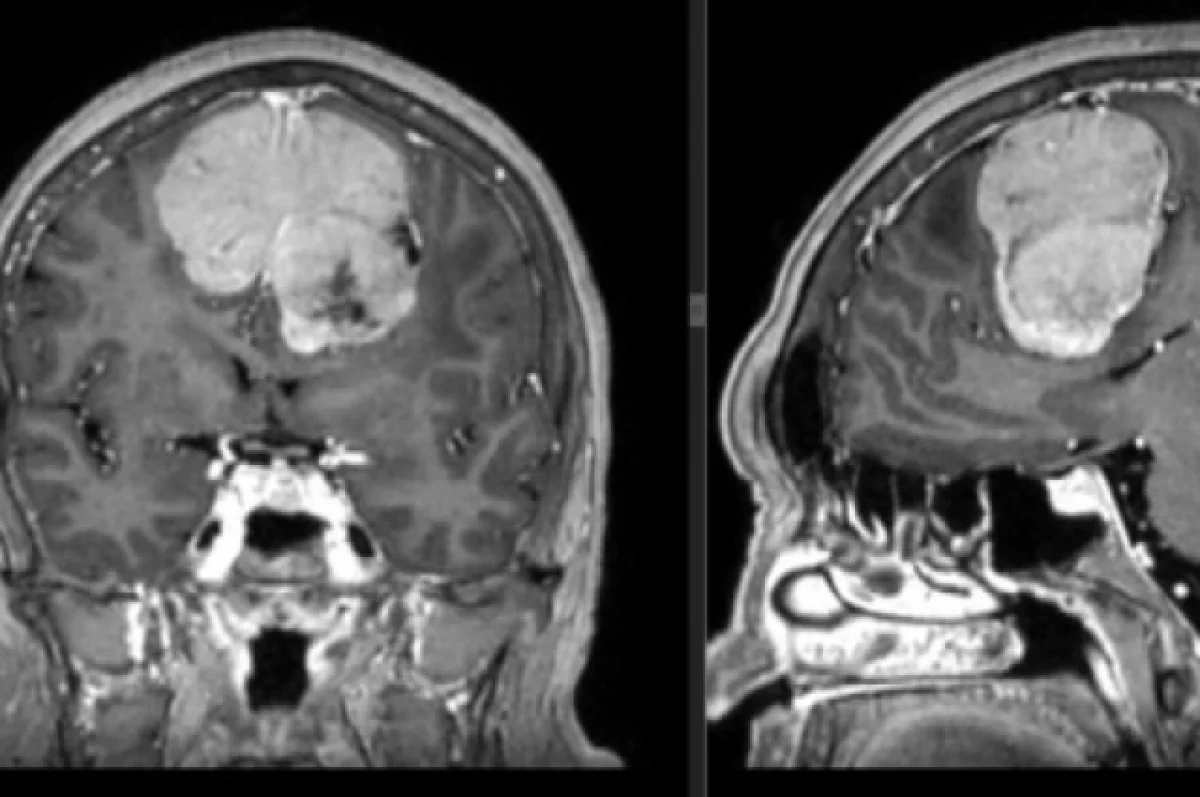

Разработан метод «химической хирургии» для удаления опухолей мозга без разрезов

Учёные представили технологию, позволяющую точечно растворять злокачественные клетки в головном мозге, вводя целевой препарат через естественные барьеры организма.

Суть метода: Пациенту внутривенно вводится препарат-«ключ», состоящий из двух компонентов. Первый компонент — наночастицы, способные проникать через гематоэнцефалический барьер и избирательно связываться только с рецепторами раковых клеток. Второй компонент — биологически инертное вещество, которое становится смертельным для опухоли только при соединении с наночастицами. «Сборка» токсина происходит непосредственно на мембране злокачественной клетки, что вызывает её мгновенный лизис (растворение). Здоровые нейроны при этом не затрагиваются.

Результат: В клинических испытаниях у пациентов с глиобластомой применение метода привело к уменьшению неоперабельных опухолей на 60–70% за один курс. Побочные эффекты, характерные для химиотерапии, отсутствовали. Метод открывает новые возможности для лечения глубоких и диффузных новообразований мозга, где традиционная хирургия бессильна, а лучевая терапия опасна.